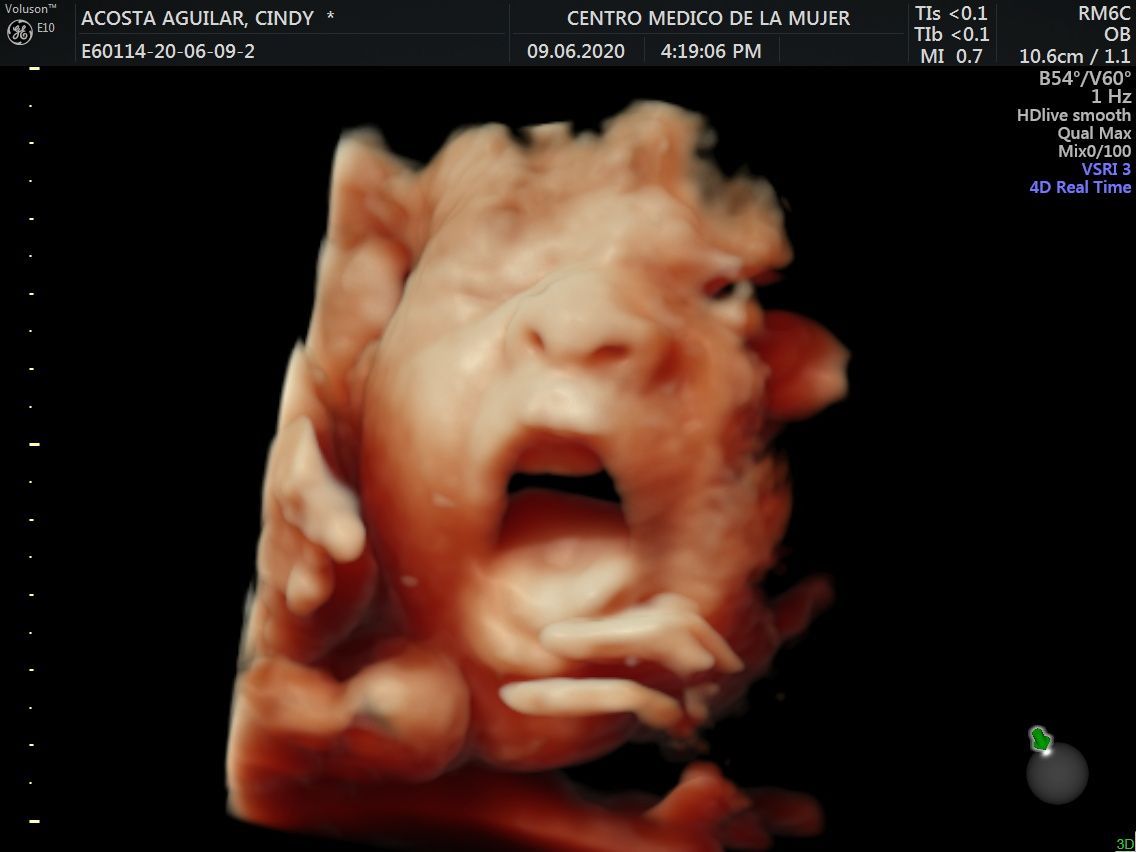

Fotos y videos

ECO Anatómico

Consiste en la evaluación especifica de cada organo y sistema del bebé con medidas detalladas de cada parte para evaluar su crecimiento proporcional.